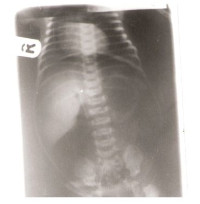

Radiological And Clinical Pattern Of Pleural Effusion In Ilorin.

A. E. Oguntoyinbo, P. O. Adeoye, G. A. Rahman, A. Y. Abdulkadir (Author)